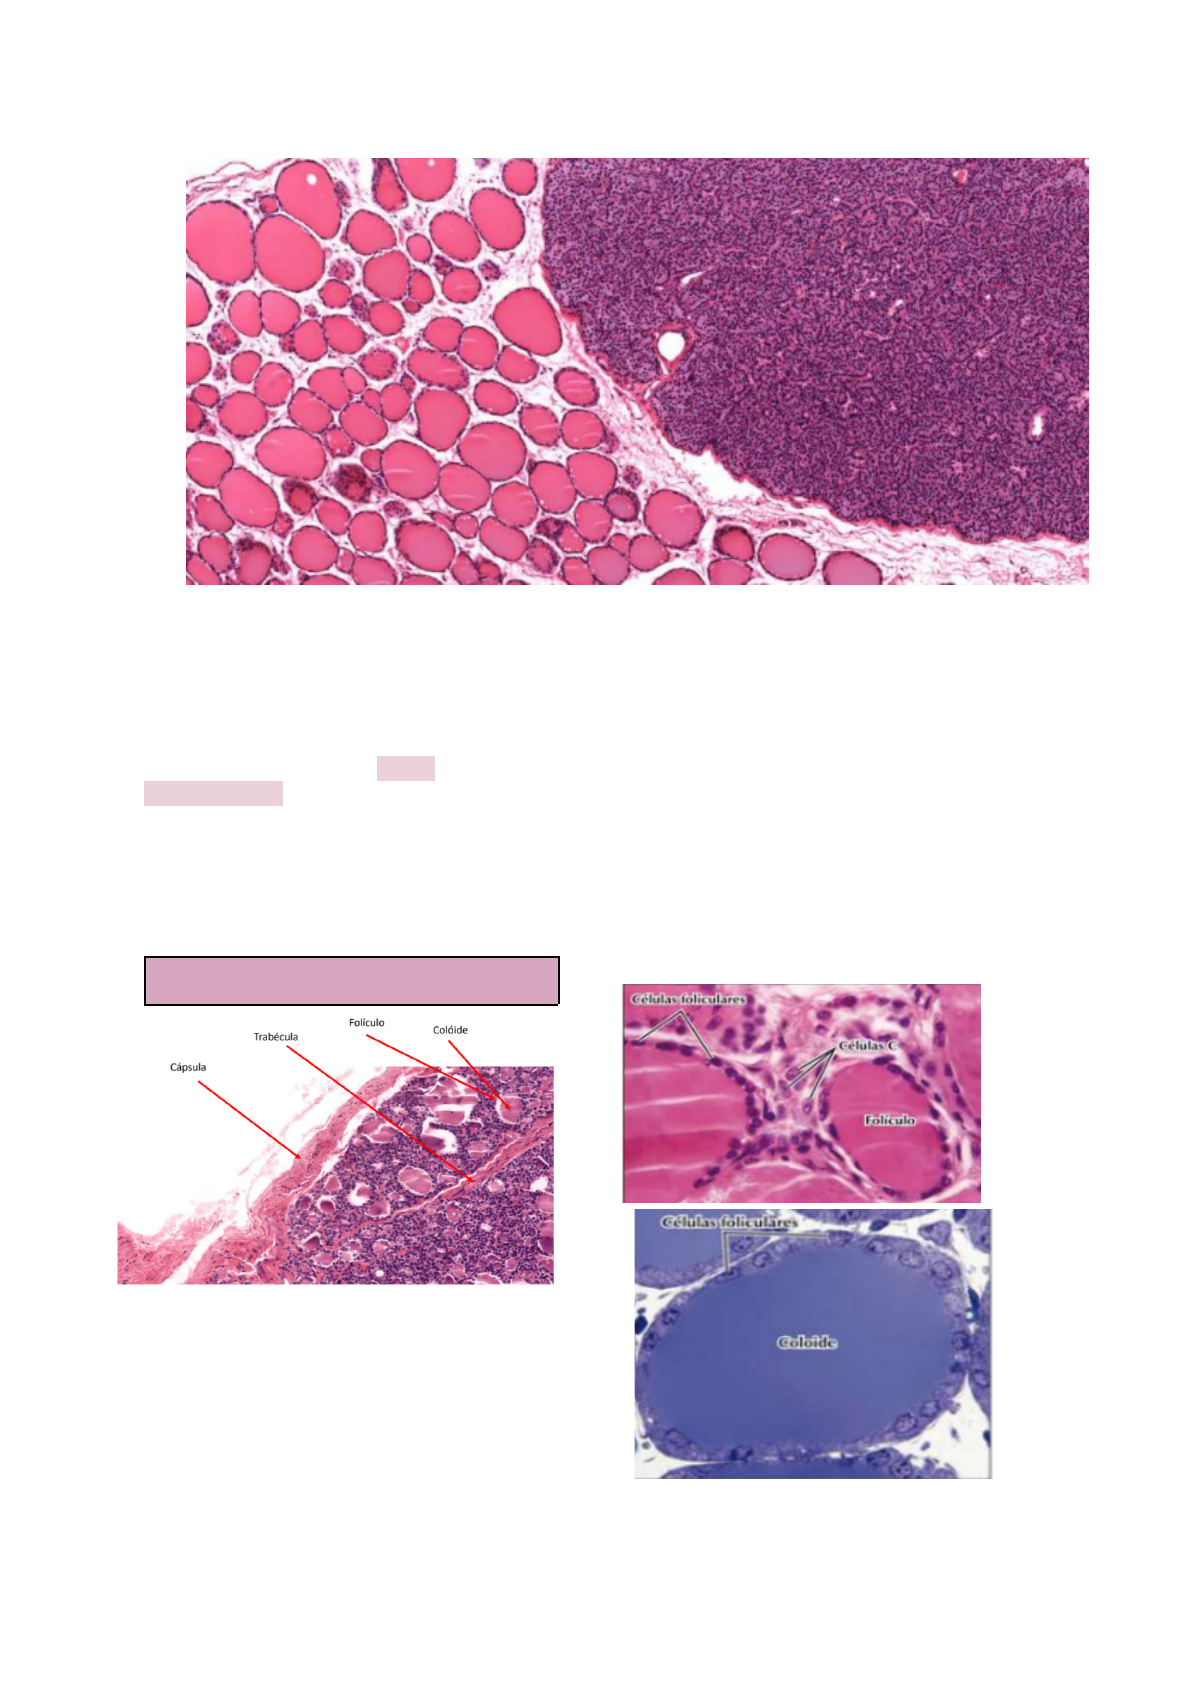

�reóid� � Paratireóid�

Trabéculas e Cápsulas da Tireóide e

Paratireóide: formadas por tecido

conjuntivo denso

Glândula Tireóide

Trabéculas

- tecido conjuntivo denso

- suporte interno

- suprimento vascular e nervoso

Fazem parte do parênquima tireoidiano:

- Células Foliculares: produzem T3, T4 (não

são nem hidro nem lipossolúveis)

- Células C/Parafoliculares (ficam entre os

folículos tireoideanos: produzem

calcitonina

- Epitélio folicular: epitélio simples cúbico

- Capilares entre os folículos: capilares

fenestrados

- Entre os folículos há tecido conjuntivo

frouxo

- A tireoglobulina fica armazenada no

colóide (cora com eosina). A porção basal

retira iodeto da corrente sanguínea e é

enviado para o colóide.

→ Cápsula: tecido conjuntivo denso

Glândula Paratireóide

Cápsula: tecido conjuntivo denso